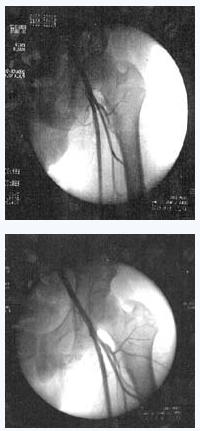

选择2010年5月至2013年5月在沈阳某医院骨外四科住院的股骨头坏死病例27例, 男21例, 女6例;年龄36~55岁, 平均40.5岁。致病原因:长期饮酒19例, 外伤后5例, 长期服用激素2例, 不明原因1例。提取培养人脐带间充质干细胞。并对患者进行髓芯减压植骨术联合脐带间充质干细胞移植干预。27例患者术后12~20个月 (平均18个月) 随访, 按Harris髋关节功能评分, 疼痛消失, 能从事各种劳动, X线片或MRI显示股骨头基本正常23髋 (76.7%) ;疼痛明显减轻, 行走基本正常或者轻微跛行7髋 (23.3%) ;行走间距延长28髋 (93.3%) , 髋关节功能障碍明显好转18髋(60%) 。

沈阳某医院的医务人员将间充质干细胞经过技术处理后注入小许的股骨头,两周后小许就可以下地行走了。10个月后,小许来医院复查,他的股骨头周围已长出丰富的血管,表明移植的间充质干细胞促使坏死变性的股骨头修复新生。